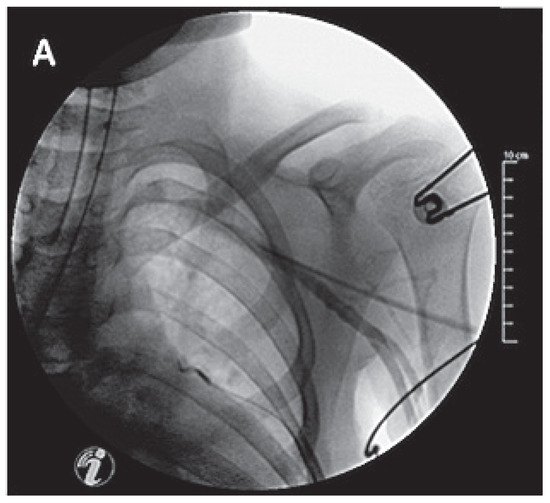

A 41-year-old women with Ebstein’s anomaly required tricuspid valve replacement six years ago. At that time a biological prosthesis was implanted. The tricuspid valve prosthesis became severely stenotic within five years. Instead of re-do surgery, th...